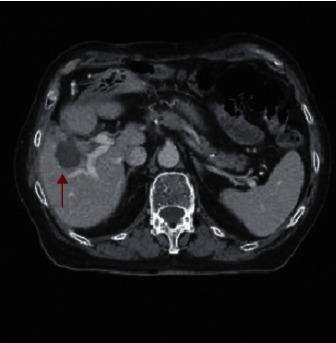

Microwave ablation is a safe and effective interventional approach, widely used in the treatment of unresectable primary or metastatic hepatic lesions. Thoracobiliary fistula is a rare postablation complication that can be treated with a conservative or surgical approach. We reviewed aetiology, pathogenesis, clinical picture, diagnostic possibilities, and therapeutic options for biliothoracic fistula developed after microwave ablation of liver metastasis. Furthermore, we reported our experience of successful conservative management of a nonhealing thoracobiliary fistula occurred after percutaneous thermal ablation of colorectal cancer liver metastasis. Our case supports a conservative approach based on percutaneous biliary system decompression and synthetic glue embolization for the treatment of combined biliopleural and biliobronchial fistula.

微波消融是一种安全有效的介入方法,广泛应用于不可切除的原发性或转移性肝病灶的治疗。胸胆瘘是一种罕见的消融后并发症,可采用保守或手术方法治疗。我们回顾了肝转移瘤微波消融术后发生胆胸瘘的病因、发病机制、临床表现、诊断方法及治疗选择。此外,我们报告了经皮热消融结直肠癌肝转移后发生的不愈合胸胆瘘成功保守治疗的经验。我们的病例支持基于经皮胆道系统减压和合成胶水栓塞的保守方法来治疗合并的胆胸膜瘘和胆支气管瘘。